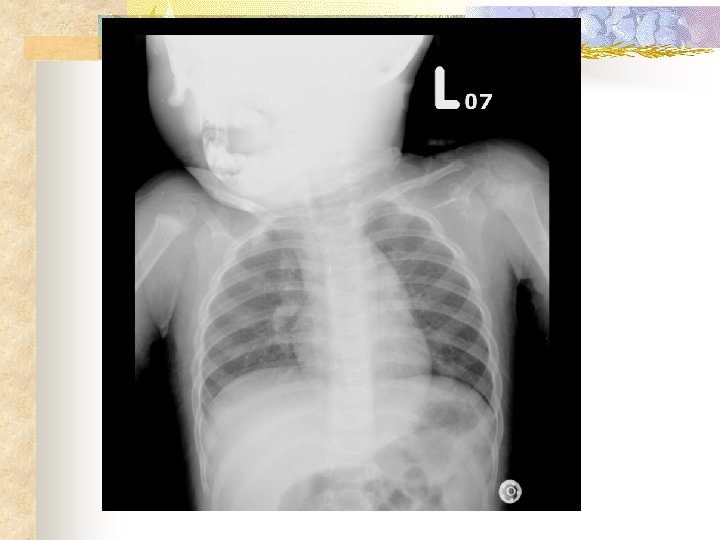

Initial order (11 min) n n Dexamethasone 1 PC IM stat, Bosmin 1 PC inhalation stat CXR, C-spine extension lateral view

Stridor assessment Neck radiographs: n Croup AP view steeple sign subglottic arch becomes edematous n Croup lateral view distended hypopharynx and subglottic haziness

Stridor assessment Neck radiographs: n epiglottitis lateral view an edematous epiglottis with the thumb sign, enlarged aryepiglottic folds, and a ballooned hypopharyngeal airway n 70 percent of all patients with epiglottitis have radiographic findings interpreted as normal